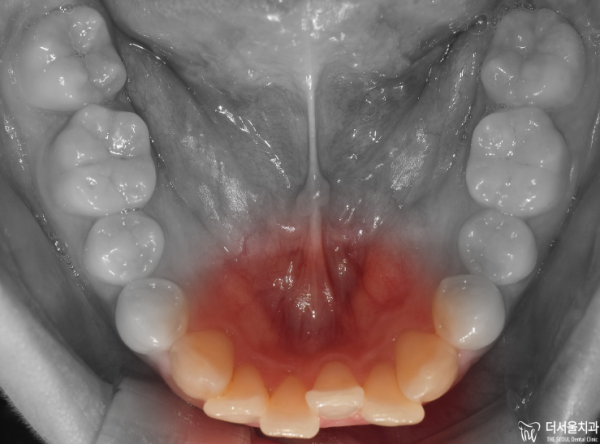

이렇게 교합면을 보면 앞니들이 위 아래 모두 삐뚤빼뚤한

총생을 보이고 있습니다.

If you look at the occlusal side, the front teeth are all crooked.

He's living his whole life.